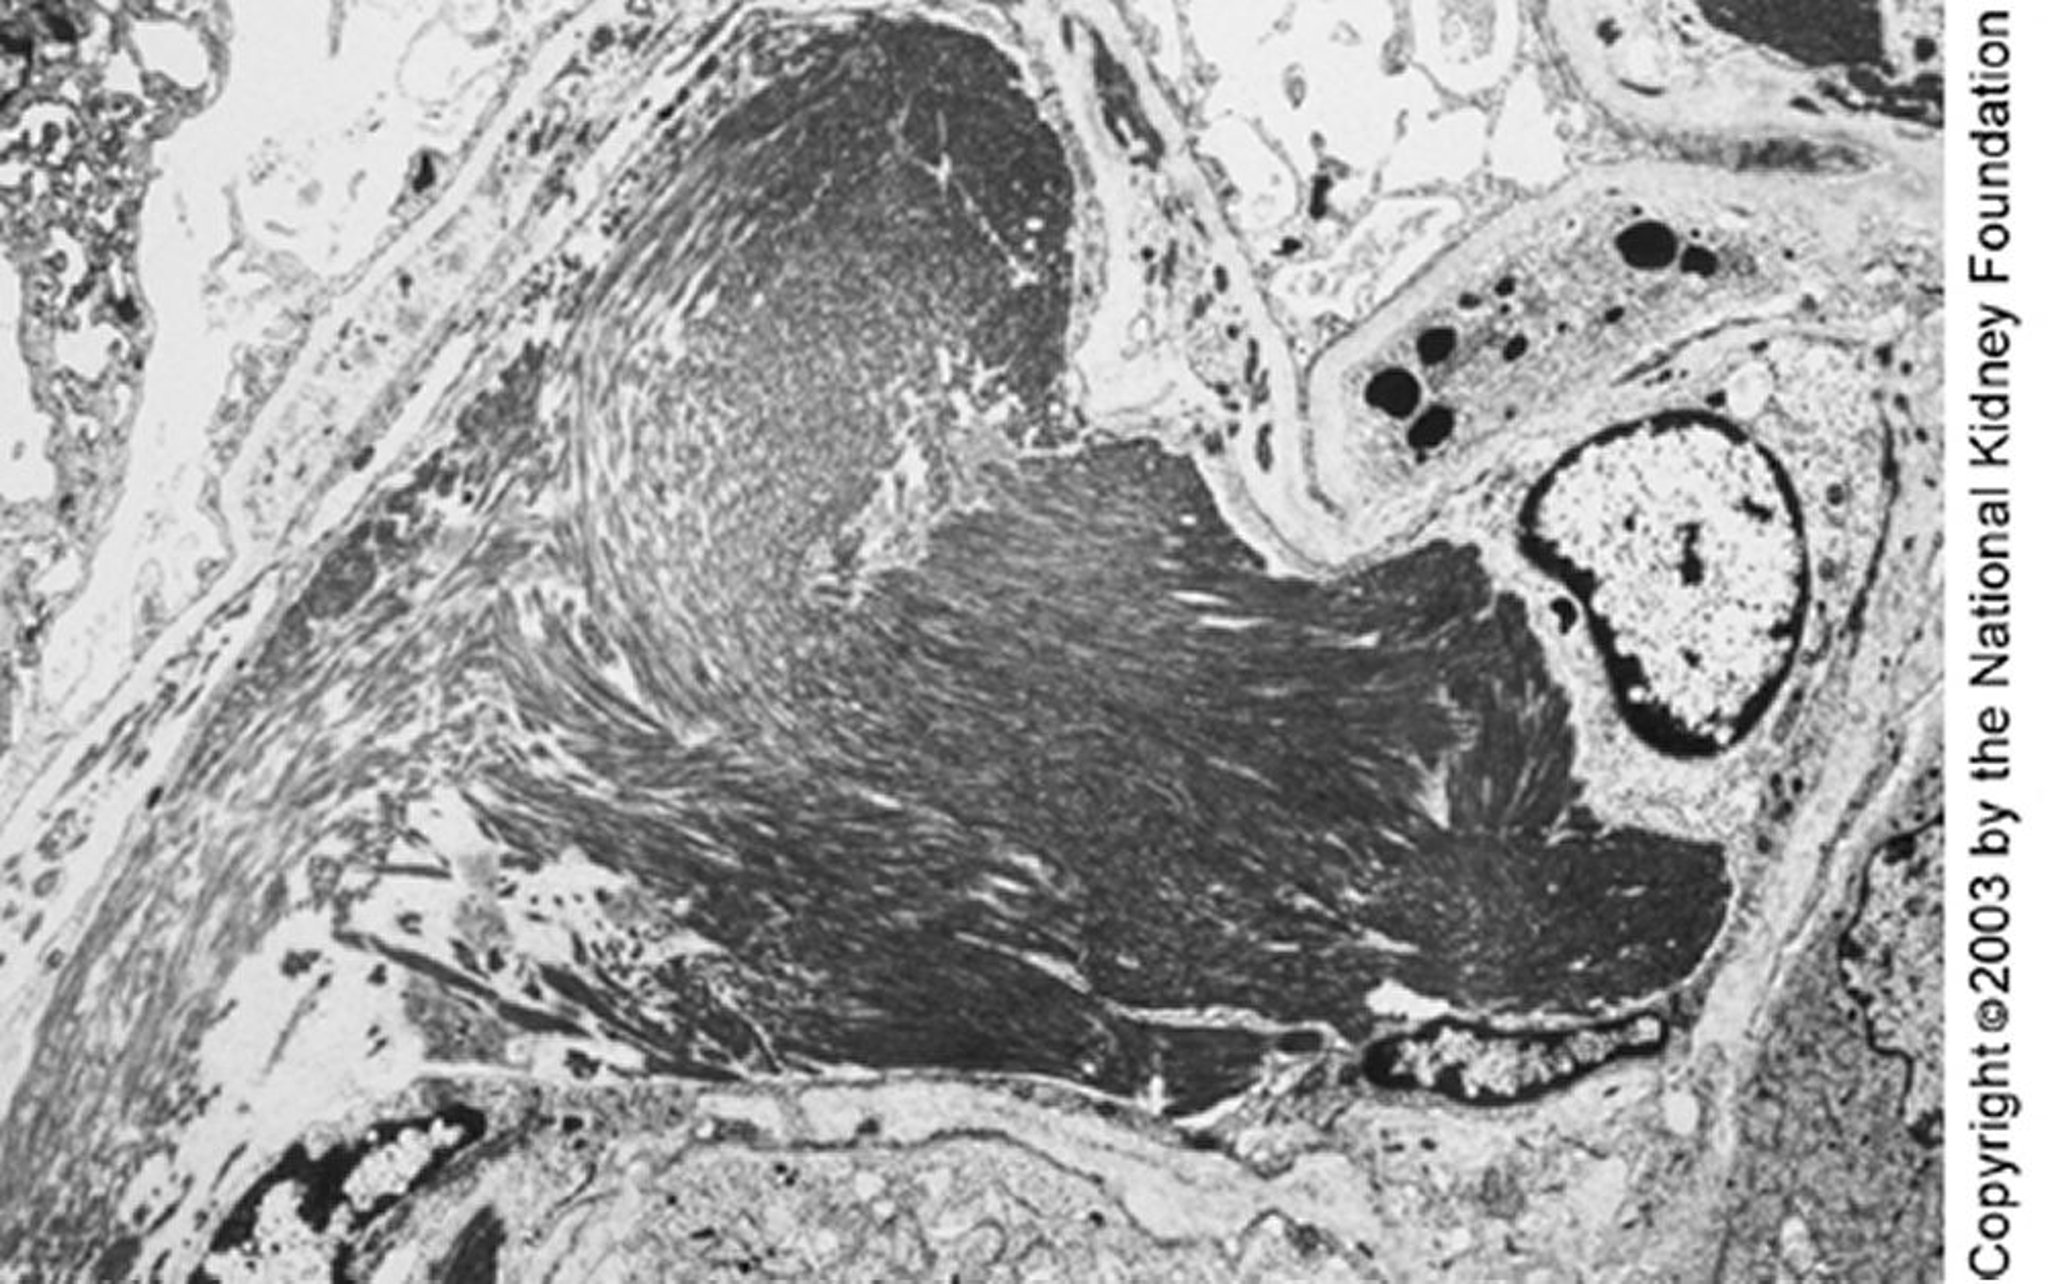

На просвечивающей электронной микроскопии можно увидеть крупные микротрубочки (диаметром около 50 нм), организованные в параллельные пучки. Иммунотактоидную гломерулопатию можно отличить от фибриллярной по характерным признакам — параллельному расположению отложений и микротрубочковой структуре (×4000).

Image provided by Agnes Fogo, MD, and the American Journal of Kidney Diseases' Atlas of Renal Pathology (see www.ajkd.org).